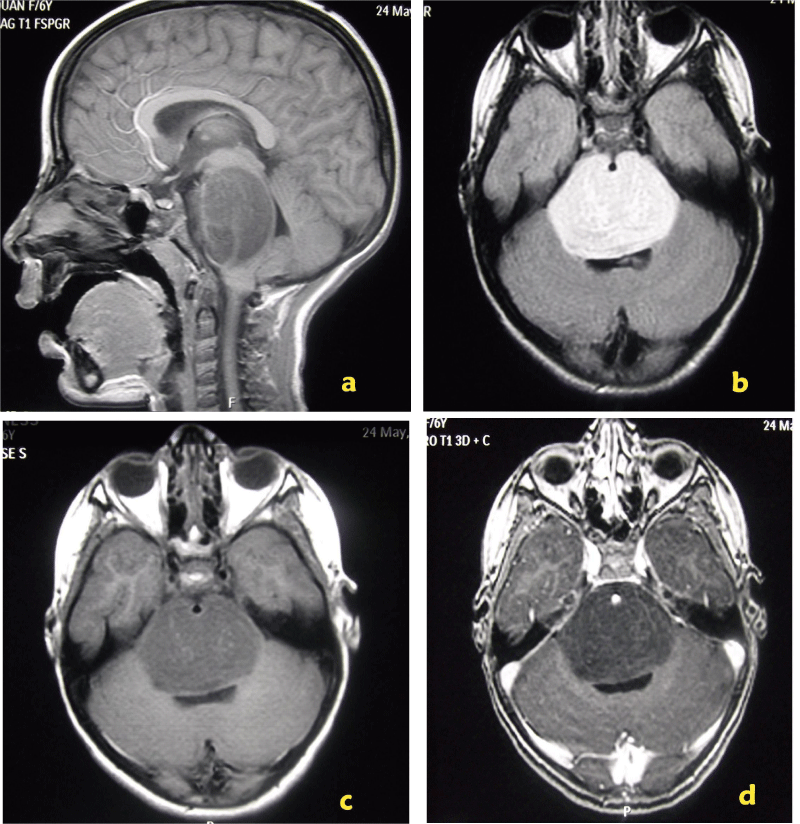

Complement MRI (combining double and three-dimensional morphological study metabolic by SRM) confirmed the presence of a pontine mass heterogeneous T1 hypointense and T2 hyperintense not enhanced after intravenous injection of gadolinium exerting a mass effect on the V4 with deletion of pre pontine cistern and circumferential engrainement the basilar artery (Figure 1). MRS (Figure 2) was a significant elevation peaks of choline and myoinositol associated with a marked decrease in N acetyl aspartate (NAA) and the ratio NAA / Creatine. The diagnosis of low-grade glioma infiltrating the brainstem was heavily discussed. The patient was supported in radiotherapy.

Figure 1: MRI. Morphological study. Sagittal T1 sequences FSPGR (a), axial T2 Flair (b) FSE T1 (c) and ESF T1 gadolinium (d). Presence of a heterogeneous hypointense mass pontine T1 T2 and not enhanced after intravenous injection Gadolinium exerting a mass effect on the V4 with deletion of pre pontine cistern and engrainement circumferential basilar.